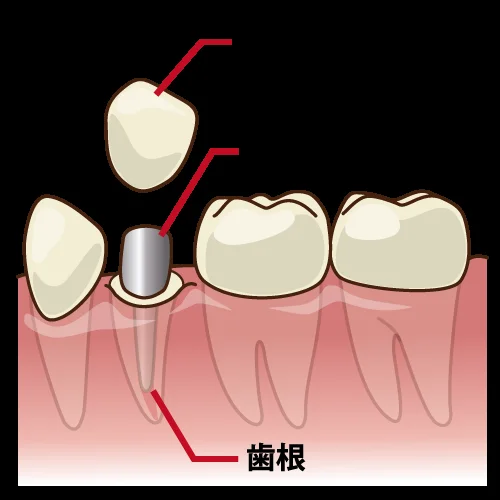

こーんな感じで

「神経の治療後はメタルコア(金属の土台)を入れる」

というのが歯科界での常識でした。

当然金属は歯よりも固いので、噛む度に楔のような作用が働き、歯が折れる主たる原因となってしまっていました。

現在では歯根破折のリスクを減らすことが出来るファイバーコアが保険適用内でも認められていますので、わざわざ歯根破折のリスクが圧倒的に高いメタルコアを入れる機会は無くなってきましたが・・・